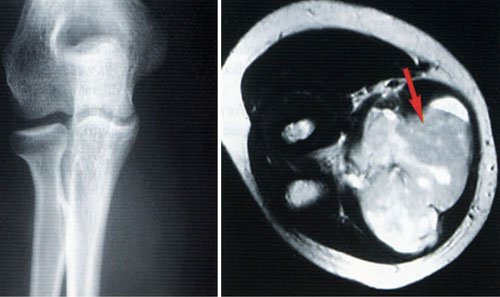

Limb Reconstruction surgeries- Removal of complete tumours with no remaining disease...

Bone tumours presented with abnormal swelling and pain at limbs, joints and back of trunk...